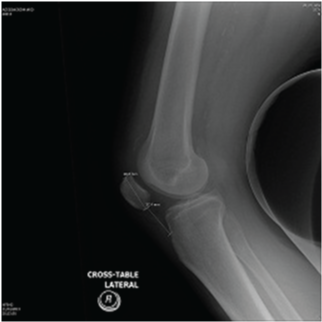

A 53 year-old male presented with history of fall down over his flexed knees while descending from stairs and complaining of bilateral knee pain, swelling and inability to bear weight. He is known to have chronic renal failure secondary to membranous glomerulonephritis for the last 15 years. He is on hemodialysis three times per week since that time. He has history of two rejected renal transplant in the last seven years. Clinical examination revealed bilateral severe effusion around the knee with tenderness to palpation. A palpable left infrapatellar and right suprapatellar gaps are detected. His knees were in 20-30 degrees of flexion with restricted active flexion due to pain and effusion. He has bilateral loss of extensor mechanism. Bilateral knee x-rays showed left knee patella alta with Insall-Salvati ratio of 0.48. Right knee x-ray showed no obvious abnormality with Insall-Salvati ratio of 1.07 (Figure 1–3).

Figure 2 Lateral right knee radiograph showing normal Insall-Salvati.